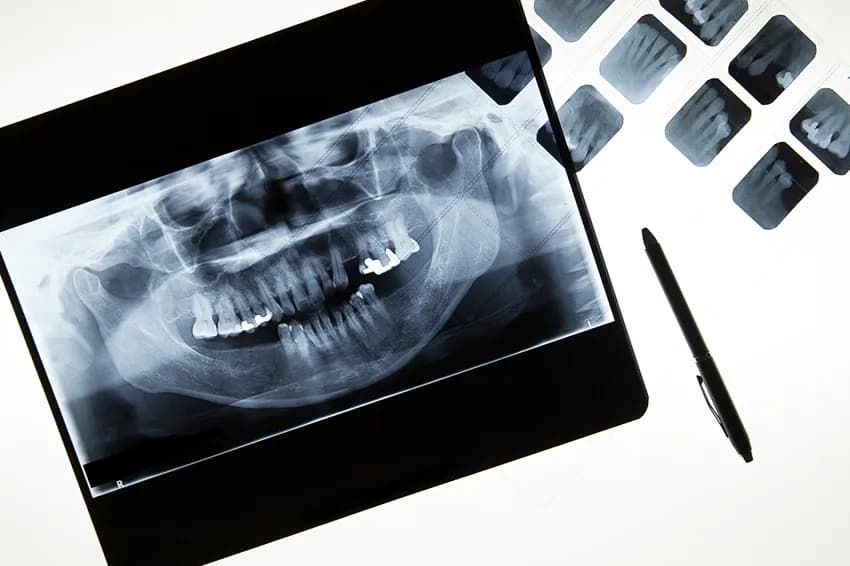

Restorative dentistry focuses on repairing or replacing damaged or missing teeth. The procedures include crowns, bridges, and implants which are all used to improve oral health and function. Tooth restoration can restore the natural function of your teeth, plus prevent additional damage from decay.

Restorative dentistry is used to repair damaged or missing teeth. This process aims to achieve optimum dental function and aesthetics for patients. The main goal of restorative dentistry is to improve oral health and chewing function. Restorative dental procedures help by: